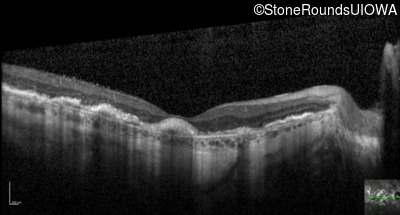

Optical Coherence Tomography - Right - 20/200 +2

Exemplar / OCT Stack

OCT Stack